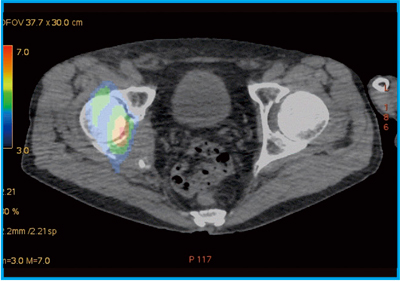

●症例5:骨肉腫化学療法後のThallium imaging

症例5は,骨肉腫化学療法の治療効果判定のためにタリウム(201Tl)シンチグラフィを撮像し,左大腿遠位にごく粗い集積が見られたが,reduction ratioは78%と著明に減少していた。集積残存の局在は不明なため,SPECT/CTを施行した。201Tl・SPECTで残存集積を緑色で表示し,CTの3D VR画像とフュージョンしたところ,viable regionが辺縁部に限局していると考えられた(図9)。

CT 3D VR画像で生検時の皮膚の傷口が認められ,フュージョン画像を皮膚面から透過して見ると傷口の高さとほぼ同じ位置に病変の残存があることが確認できた。CTの併用により,局在を明らかにできるメリットは大きいと言える。

図9 症例5:骨肉腫化学療法後のCT 3D VR画像とSPECTのフュージョン画像